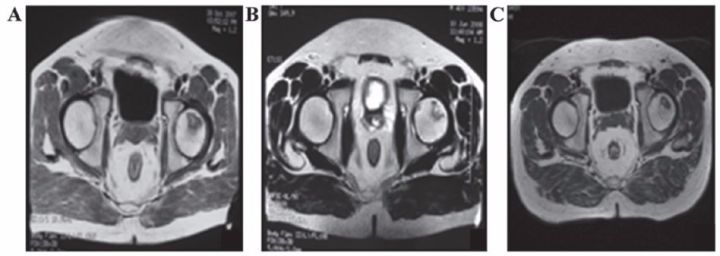

7、運動系統疾病

?股骨頭壞死

間充質干細胞移植治療人體股骨頭壞死在國外已有報道。法國科學家移植治療116例股骨頭壞死患者效果顯著,其中87.3%的患者髖關節疼痛緩解;78.4%的患者關節功能改善;80%的患者行走間距延長。

沈陽463醫院的楊曉鳳主任將間充質干細胞經過技術處理后注入小許的股骨頭,兩周后小許就可以下地行走了。10個月后,小許來醫院復查,他的股骨頭周圍已長出豐富的血管,表明移植的間充質干細胞促使壞死變性的股骨頭修復新生。

表8 劉穎、谷涌泉應用臍帶MSC治療股骨頭壞死的臨床研究結果

吉林省組織工程重點實驗室劉穎教授 、首都醫科大學宣武醫院谷涌泉主任等,對9位骨循環協會評級為II-IIIa級的股骨頭壞死患者經大腿動脈輸注臍帶間充質干細胞后,患者的紅細胞、血小板、血氧轉運指數明顯改善。MRI檢測顯示24個月后股骨頭壞死區域體積顯著減少。